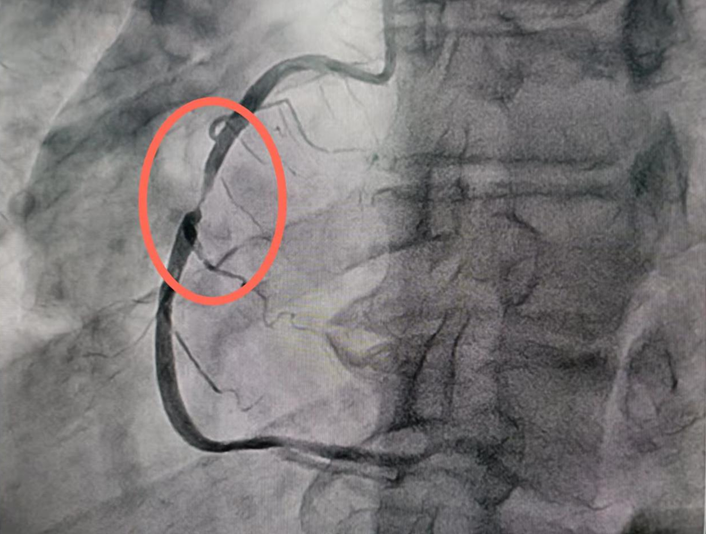

冠心病的介入治疗

冠心病的介入治疗,主要包括冠状动脉造影术、经皮冠状动脉球囊血管成形术(PTCA)、冠状动脉支架植入术(PCI)等。冠状动脉造影术即是在数字减影机下使用导管在冠状动脉内推注照影剂,检查冠状动脉有没有粥样硬化引起的狭窄,血流动力学的改变。冠状动脉球囊血管成形术是通过外周动脉,将指引导管送至待扩张的冠状动脉口,再将相应大小的球囊沿导引钢丝送到冠脉狭窄的节段,根据病变的特点用适当的压力和时间进行逐渐扩张,利用钝性扩张达到解除狭窄的目的。但是单纯PTCA可能会造成冠状动脉急性闭塞以及再狭窄的发生率较高。冠状动脉支架植入术与PTCA相同的是同样需要将相应大小的球囊沿导丝送入冠状动脉狭窄的节段,但不同在于球囊外有可扩张支撑的网状带间隙支架,随着球囊扩张,支架在冠状动脉内狭窄处扩张,球囊撤走后,支架留在冠脉内支撑血管壁,维持血流通常。

心病科自2011年开始开展冠心病科的介入治疗,相继开展了血管内超声检查(IVUS)腔内影像学检查及冠脉血流储备分数(FFR)功能学检查。尤其在急性心肌梗死的介入治疗、多支复杂病变、左主干病变、分叉病变及陈旧闭塞病变(CTO)的介入治疗达到国内先进水平。每年完成手术800余台次。

手术后